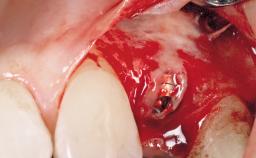

Early Placement of an Implant in a Maxillary Right Central Incisor Site

This 41-year-old female patient was referred to the clinic for the replacement of the right central incisor, since the tooth had developed a root fracture in the long axis that made extraction necessary. The healthy, non-smoking patient was first seen with the tooth still in place. A detailed Esthetic Risk Assessment was performed.The patient was worried about her dental esthetics and had high expectations for a successful treatment outcome from an esthetic point of view. The patient had a medium lip line that displayed parts of the gingiva in the anterior maxilla upon smile.

Esthetic Risk High